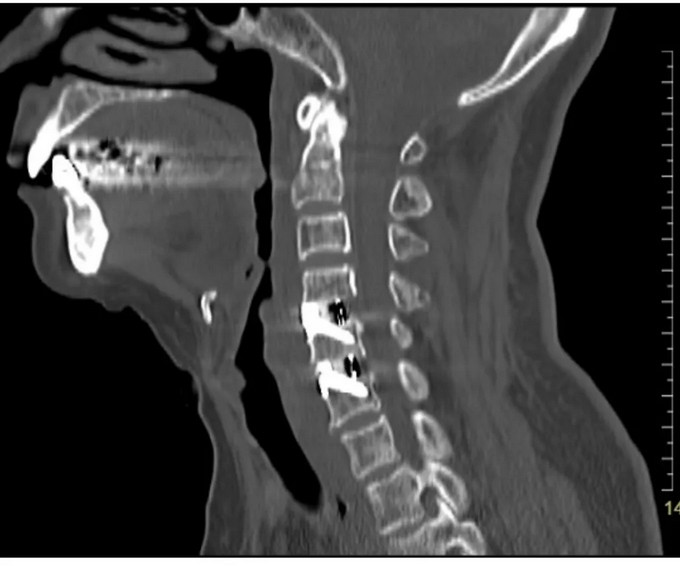

術前影像

頸椎CT矢狀位